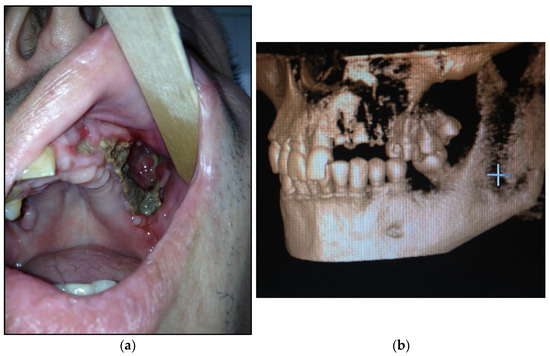

- Type 4: patients with maxilla, zygomatic bone, floor of the orbit involved—10 patients (20%) (Figure 4a,b)Figure 4. (a) Patient with type 4 toxic phosphorus osteonecrosis. Intraoral view; (b) multi CT-scan of patient’s skull before operation.Figure 4. (a) Patient with type 4 toxic phosphorus osteonecrosis. Intraoral view; (b) multi CT-scan of patient’s skull before operation.